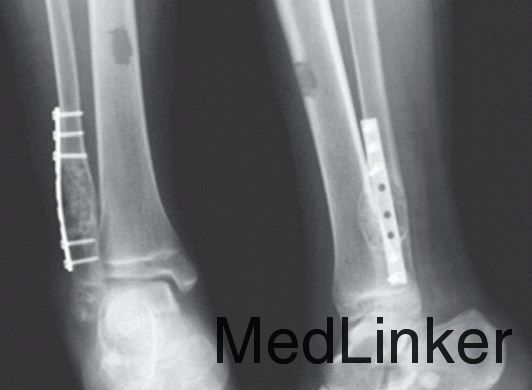

男,15岁,右踝部间断疼痛2年,加重伴右踝部肿胀1周。查体:右外踝上6cm处略肿胀,局部皮温正常,未触及包块,局部压痛明显,右踝关节活动度基本正常。右胫腓骨正侧位平片(图1):右腓骨远端干骺端膨胀性骨破坏,骨密度减低,骨皮质变薄,病灶内有分房,未见骨膜反应及周围软组织影。胫骨中下段髓腔内可见类圆形影,边界清楚,骨皮质无破坏。右踝MRI示:腓骨下段髓腔内显示4.5cm×2cm等T1、短T2异常信号灶,边界清楚,信号不均,其内可见分隔,病灶呈膨胀性生长,骨皮质变薄(图2)。右胫骨中下段髓腔内显示3.7cm×1.7cm椭圆形长T1、T2信号灶,边界清楚,信号均匀,边缘规则,骨皮质连续。结合病史及影像学表现考虑为良性病变,遂在硬膜外麻醉下行右腓骨远端病灶刮除、异体骨植骨、内固定术,右胫骨病灶刮除术。术后病理报告:(1)右腓骨远端髓腔内有5cm×4.5cm×1.3cm肿块。镜下见大片的梭形细胞伴有较多体积较大的多核巨细胞,局部见新生的骨小梁样结构,结合临床,考虑为GCT(图4)。(2)右胫骨远端髓腔内见灰黄色结节肿物,总体积3.5cm×3cm×1cm,镜下显示成熟的脂肪细胞并见增生小血管,结合临床考虑血管脂肪瘤(图5)。术后2周切口愈合良好,无红肿渗出现象,术后3个月患肢行走步态接近正常。术后10个月X线片见腓骨植骨融合,无明显骨破坏,胫骨开窗处可见骨修复(图6)。